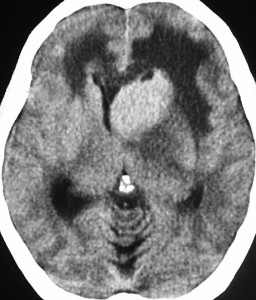

単純CT(左側の画像)で腫瘍の部分が少しだけ高吸収値域を示す(ちょっと白っぽくなる)のが大きな特徴で,この所見をもってグリオーマとの区別をします。周囲に黒っぽい部分がありますが,これは脳の腫れで脳浮腫と言います。右側のCTは造影剤を入れたものでよりはっきり写ります。